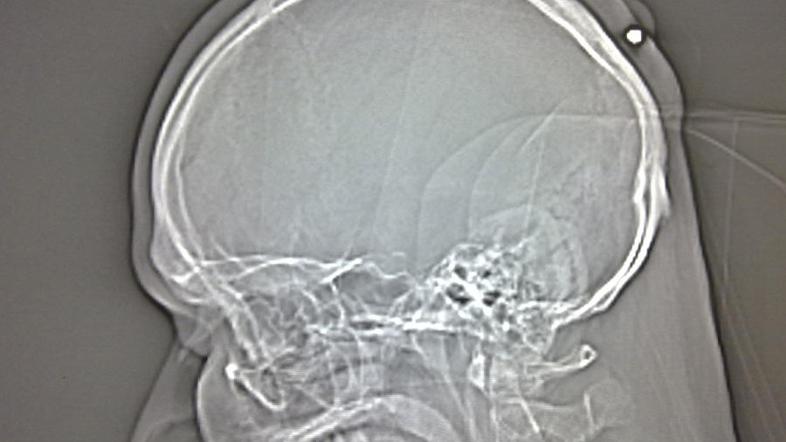

Policija iz mesta Bochum je sporočila, da so zdravniki pri 35-letnem Poljaku naboj v zadnjem delu glave našli potem, ko je bil ta prepričan, da mu bodo na operaciji odstranili cisto.

Ko pa so mu pokazali 5,6-milimetrski naboj, pa se je spomnil, da ga je na praznovanju novega leta "leta 2004 ali 2005" nekaj zadelo v glavo, ampak je na to pozabil, ker je bil "čisto pijan", je dejal tiskovni predstavnik policije.